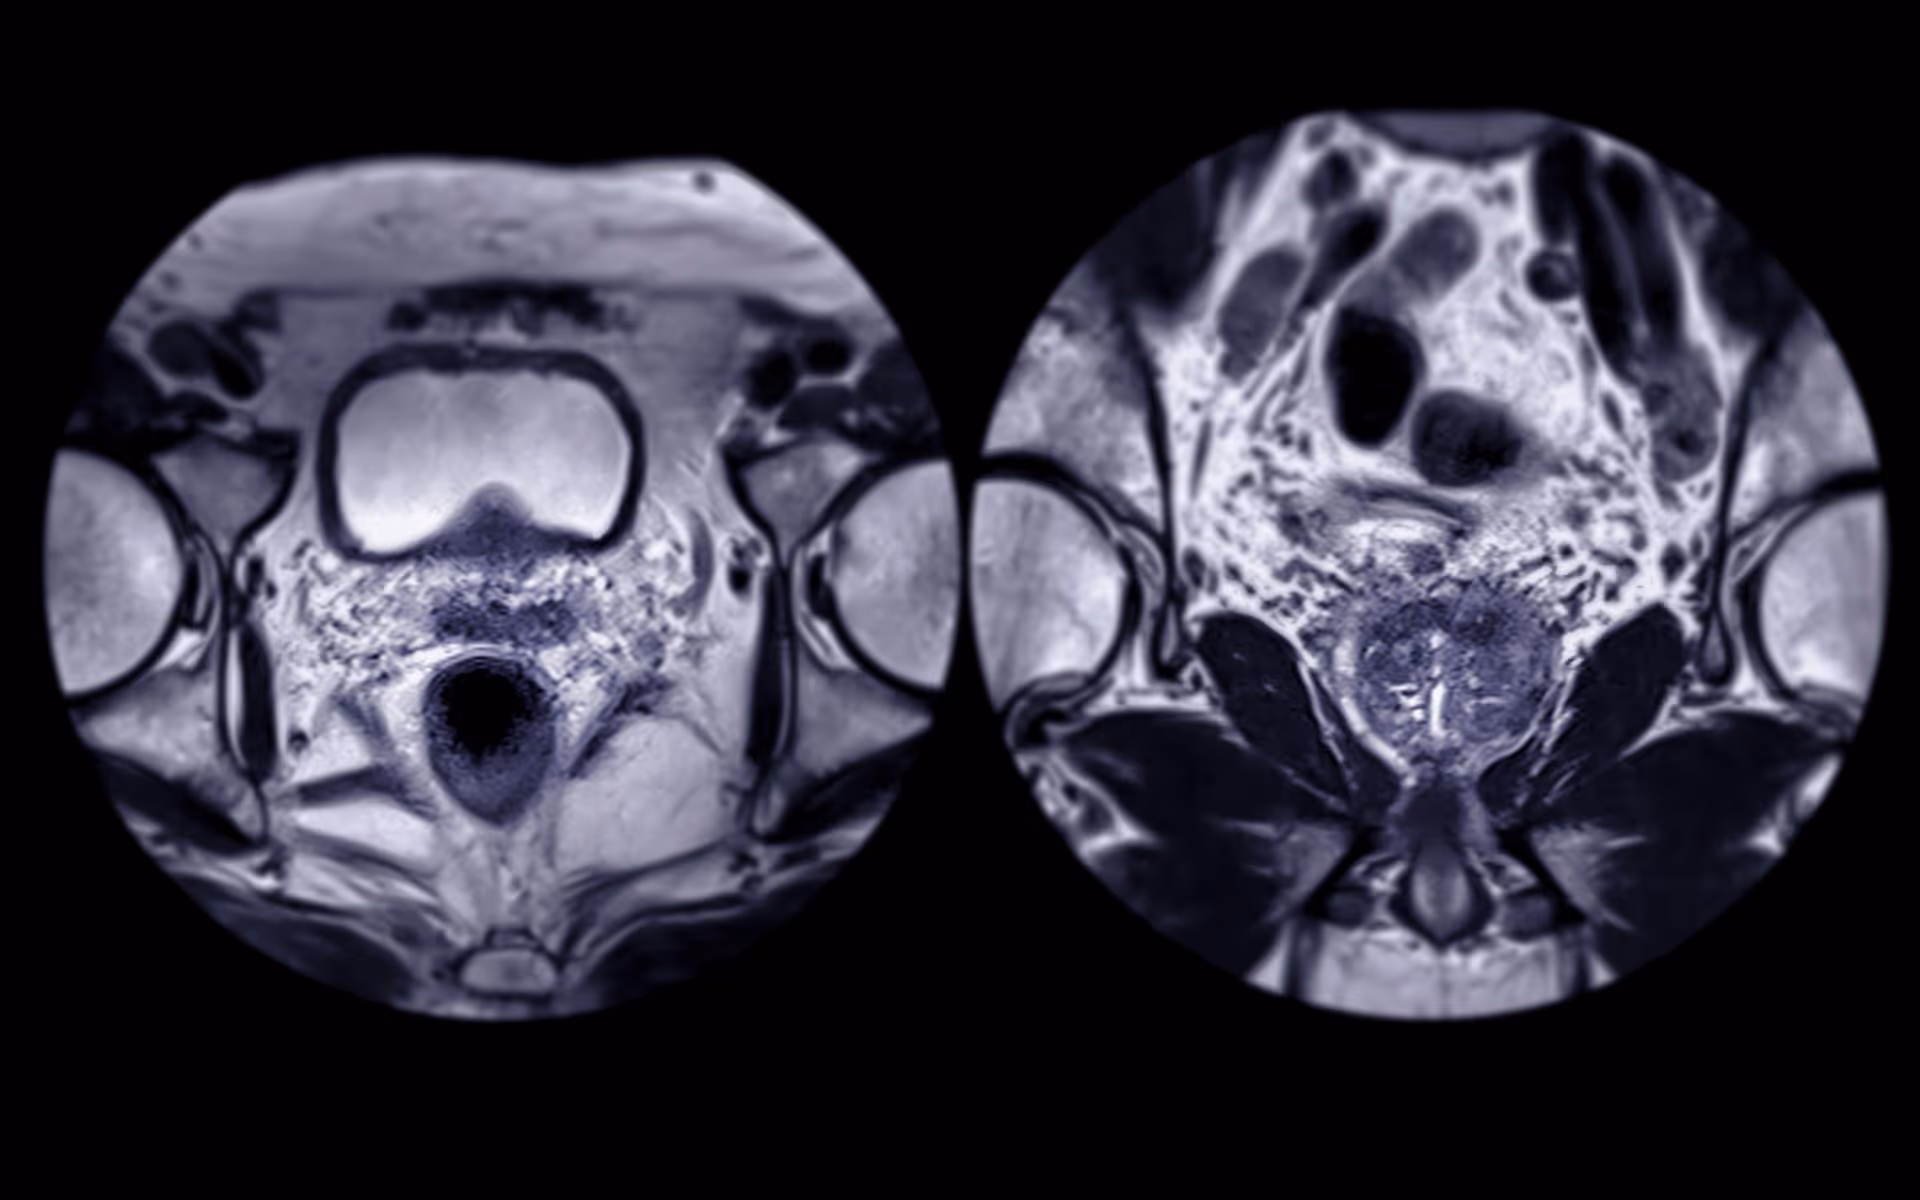

MRI, ultrasound, and cutting-edge technology for accurate diagnostics.

- Precision: Enhances treatment planning by mapping cancer locations.